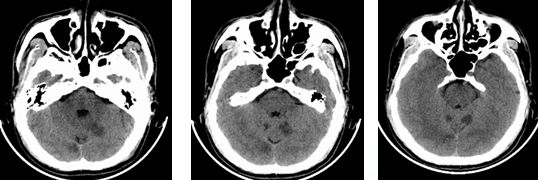

入院时颅脑CT(3.19)小脑梗塞

03-19,14时30:入院

03-20,11时:病情加重,请神经介入科 会诊

03-20,12时:行股动脉穿刺,血管内治疗

术后复查颅脑CT